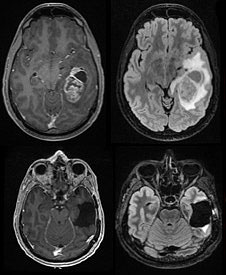

MRIs of brain tumor before and after surgical removal

MRI of glioblastomas.

In one paper, research teams led by Wendell Lim, PhD, chair and Byers Distinguished Professor of cellular and molecular pharmacology, and Hideho Okada, MD, PhD, the Kathleen M. Plant Distinguished Professor of neurological surgery, tested the system in glioblastoma, the most aggressive form of brain cancer that affects adults and children, and which physicians have yet to successfully treat with immunotherapies due to the complexity of the tumors. The team showed the new system, which uses a two-step process to hunt down cancer cells, could completely clear human patient-derived tumors from the brains of mice without the dangerous side effects or high risk of recurrence currently associated with immunotherapy treatment in solid tumors.

Glioblastomas are a particularly tragic case in which patients so far haven’t been able to benefit from CAR-T cells. Every year, over 20,000 adults in the United States are diagnosed with glioblastoma or other types of malignant brain cancer, and with current treatments, the prognosis is grim.

Experiments described in the paper show that this strategy is effective. In mice with human patient-derived glioblastomas, synNotch CAR-Ts wiped out tumors that weren’t cleared by normal T-cells or traditional CAR-Ts, with no signs of dangerous side effects.